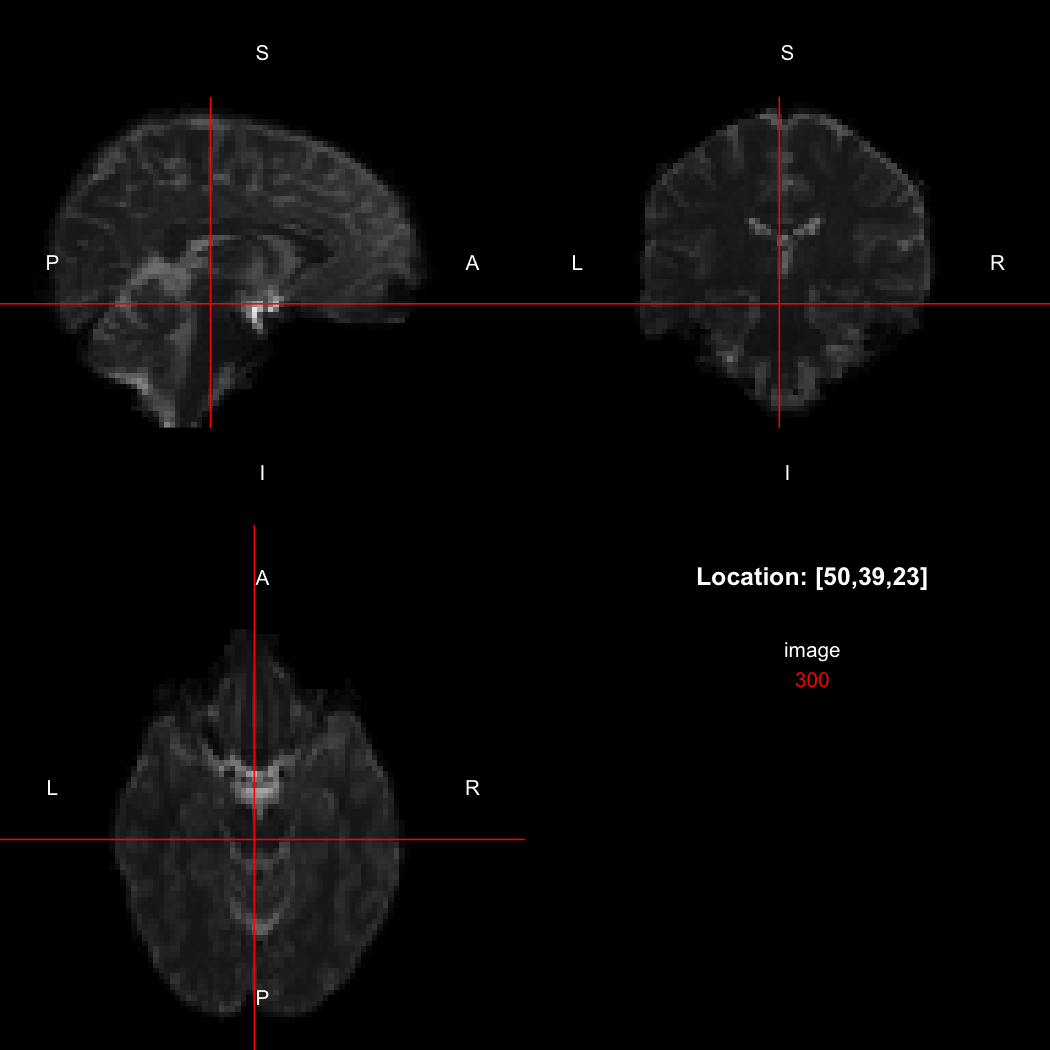

The package contains a basic image viewer, which can be used interactively or noninteractively to examine 2D or 3D images.

view(image)

plot of chunk unnamed-chunk-5

By default, the viewer shows labels indicating image orientation, crosshairs pinpointing the currently selected location, the numerical indices of the current location, and the value of the image at that location. Options allow each of these to be turned off, for the content of the bottom-right panel to be customised entirely, for the colour scale to be changed, and for additional images to be layered on top of the base image. See ?view for details.

image[50,39,23]

## [1] 300